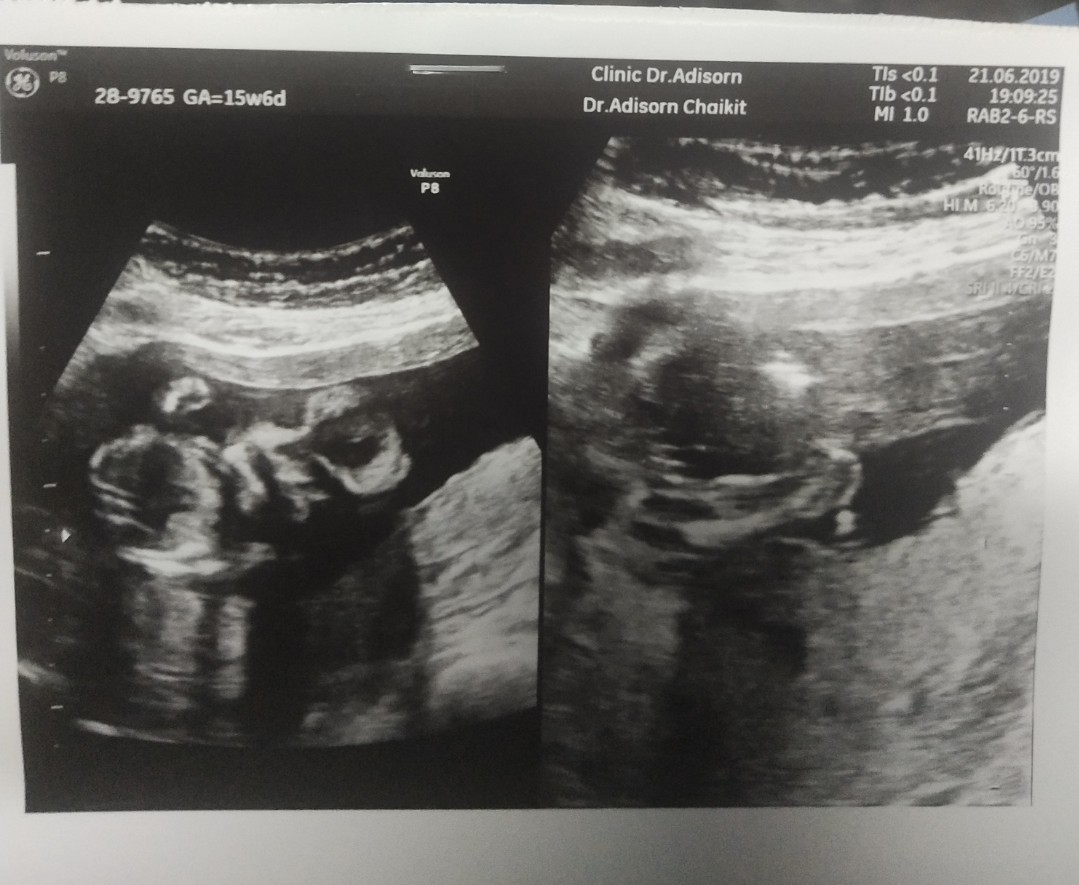

พึ่งซาวไป(19w)เมื่อ 21 มิย. เพื่อเจาะน้ำคร่ำค่ะ หมอบอกว่าที่ยื่นออกมาคือจู๋ครับ